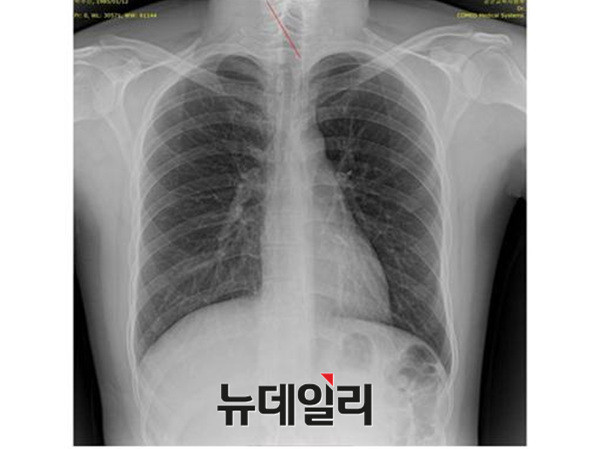

이날 뉴스데스크는 “(양승오 박사 등 피고인들은) 주신씨가 지난해 영국 유학을 앞두고 비자발급용으로 찍은 가슴 방사선 사진과, 자생병원에서 병역면제용으로 촬영한 흉부 엑스레이 사진은, 흉추의 극상돌기와 석회화 소견 등이 모두 일치하지 않는다고 주장하고 있다”고 전하면서, 양승오 박사 재판의 핵심 증거인 ‘박주신씨 명의의 엑스레이’ 비교·판독을 통해 드러난 차이점을 설명했다.

- ▲ 박주신씨 명의의 자생병원 엑스레이(왼쪽)와 공군훈련소에서 촬영된 엑스레이(오른쪽). 자생병원의 엑스레이에선 '석회화 현상'이 발견되지만, 공군 엑스레이에선 보이지 않는다. ⓒ 뉴데일리DB

최대집 의혁투 공동대표는 이 기자회견에서 “2011년 12월 자생병원에서 찍은 엑스레이에서는 우측 제1늑골에 석회화 소견이 발견되고, 흉추 1번 극상돌기 역시 수직방향으로 배열돼 있지만, 공군 엑스레이와 비자발급용 세브란스병원 엑스레이에서는 석회화 현상이 발견되지 않았고, 극상돌기 역시 오른쪽 방향으로 배열돼 있다”고 설명했다.

나아가 ▲흉추 1번, 경추 7번의 추궁판과 극돌기 밑단의 형태 ▲견갑골 견봉의 두께 ▲견갑골 오구돌기와 관절와(關節窩) 평면과의 각도 등에서 큰 차이가 발견된다고 강조했다.

지난 7월 양승오 박사 재판 3차 공판에 증인으로 출석한 세브란스병원 교수들도, ‘석회화 현상’과 ‘극상돌기 방향’에 대한 판독 결과, 박주신씨 명의의 자생병원 엑스레이와 공군훈련소 입소 당시 촬영된 엑스레이 사진이 다르다는 점을 인정했다.

반면 지난해 12월부터 시작된 양승오 박사 등 시민 7명에 대한 공직선거법 위한 공판을 통해 새롭게 밝혀진, 박주신씨의 ‘공군훈련소 입소 당시 엑스레이’(촬영일자 2011년 8월 30일, 이하 공군 엑스레이)와, 주신씨가 ‘비자발급을 위해 촬영한 세브란스병원 엑스레이’(촬영일자 2014년 7월 31일, 이하 비자발급용 엑스레이)는 각각 박주신씨 본인의 신체를 촬영한 것으로 받아들여지고 있다.

- ▲ 박주신씨 공군훈련소 입소 당시 촬영된 엑스레이. ⓒ 뉴데일리DB

- ▲ 박주신씨가 지난해 7월 비자발급을 위해 촬영한 엑스레이. ⓒ 뉴데일리DB

이들 세 개의 엑스레이는 모두 박주신씨의 신체를 촬영한 것으로 알려져 있기 때문에, 이들 엑스레이에 대한 판독결과 피사체를 동일인으로 볼 수 없는 유의미한 차이점이 발견된다면, 이는 박주신씨의 대리신검 혹은 영상자료 바꿔치기 의혹을 뒷받침하는 결정적 단서가 된다.

세계적 권위를 인정받은 영상의학 전문의인 양승오 박사(동남권원자력의학원 암센터 핵의학과 주임과장)와 치과의사 김우현씨 등 박주신씨 병역비리 의혹을 주장해 온 시민들은, 위에서 언급한 세 개의 엑스레이에 대한 비교 판독 결과, 이들 엑스레이를 같은 사람의 것으로 볼 수 없는 차이점을 발견하고 이를 재판부에 증거자료로 제출했다.

‘석회화’와 ‘극상돌기’

‘석회화’란 나이가 들어 뼈에 발생하는 퇴행성 증상의 하나로 질병이라고 볼 수는 없지만 한 번 생기면 없어지지 않으며, X-Ray를 통해 확인할 수 있는 것으로 알려졌다.

- ▲ ▲박주신의 자생병원 X-Ray(왼쪽)과 공군 X-Ray(오른쪽). 자생병원의 엑스레이에서는 오른쪽 제1늑골부위에 '석회화'현상이 보이지만 공군엑스레이에선 보이지 않는다. ⓒ 뉴데일리DB

박주신씨의 자생병원 X-Ray를 보면, 오른쪽 제1 늑골부위에 ‘석회화’ 현상이 나타난다. 그러나 주신씨가 공군 입대 당시 찍은 X-Ray에는 이런 모습이 전혀 보이지 않는다.

이런 차이에 대해 양승오 박사의 변호인인 차기환 변호사 등은 "각각의 X-Ray를 찍은 사람이 동일인이 아니라는 것을 입증한다"고 설명했다.

‘극상돌기’의 경우에도 차이점은 명확히 드러난다.

변 호인 측은 “공군에서 찍은 엑스레이와 비자발급을 위해 찍은 엑스레이에서는 피사체의 제 1흉추 극상돌기가 오른쪽으로 휘어있지만, 자생병원에서 찍은 영상에서는 정방향으로 나온다”며, “박주신씨가 공군에 입대해 찍은 엑스레이와 세브란스 공개신검에서 나타난 피사체의 의학적 차이가 명확해 동일인이라고 인정할 수 없다”고 지적했다.

우리가 흔히 등을 만지면, 가운데 뾰족하게 솟아난 부분이 바로 ‘극상돌기’다.

흉추를 비롯해 모든 척추에 존재하며, 흉추에 외상이나 수술, 질병 등이 없었던 근접한 기간 동안 촬영된 엑스레이에서 극상돌기의 형태가 명확하게 다를 경우, 다른 개체라고 판단할 의학적 근거가 된다.